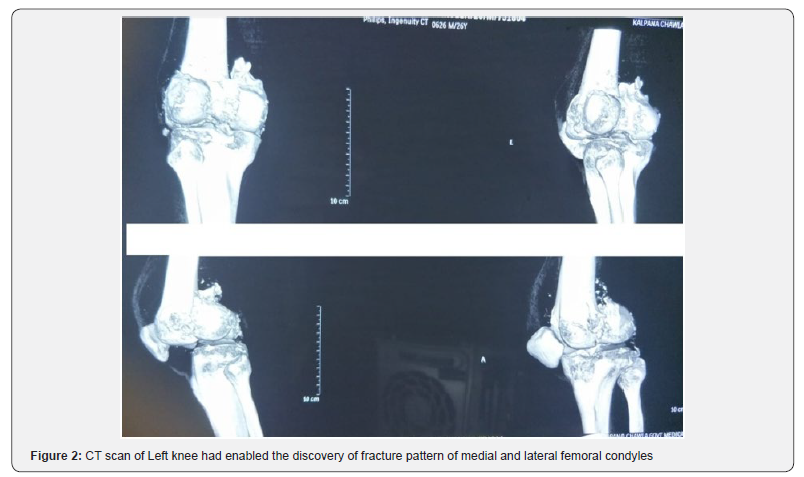

It was 26 years old male patient admitted to the Emergency Department for injury to left knee following a Road Traffic Accident which occurred about 1 month back. Patient went to a local bonesetter who applied splintage using cardboard and crepe bandage. It was a late presentation of injury and revealed painful swelling of the knee with hemarthrosis, more intense pain sitting at the level of the internal compartments of the knee. There was no neurovascular deficit or skin lesion. Because of the pain we had sought signs of laxity. The initial AP and lateral x-rays showed a bicondylar Coronal fracture (Figure 1). The CT scan showed Coronal fractures type Hoffa of the both condyles (Figure 2).

Standard AP radiograph may appear unimpressive owing to intact anterior part of condyle; moreover, undisplaced fracture may not be apparent in lateral radiograph. Oblique radiographs and CT scans have been recommended to facilitate the diagnosis of these injuries. CT scan with 3-D reconstruction helps in identifying the exact site of fracture, presence of comminution and assists in preoperative planning. The medial condyle is quite special for our patient as the bibliography suggests that the lateral condyle is most often injured [3,6]. Probably because of following physiologic genu valgus that puts greater compressive stresses on the lateral side. The usual mechanism is postulated to be a combination of vertical shearing and twisting forces. Frontal impact on a flexed knee is more likely to involve the outer aspect resulting in shearing force on the posterior part of lateral femoral condyle.

In these cases, the contribution of the CT scan is undeniable: confirms diagnosis, detect comminution, and research associated injuries. As they are intra-articular fractures, they should be treated by anatomical reduction, rigid internal fixation and early mobilization to restore function. Some authors [3,5,7] recommend open reduction to restore normal condylar anatomy and rigid internal fixation. The articular surface is exposed through a medial or a lateral approach, depending on which condyle is involved. Hoffa fractures are typically reduced and fixed with anterior-posterior or posterior-anterior orientedscrews [3,8,9]. Problems of this surgical approach are infectious hazards, devascularization and also fragment necrosis. Nowadays treatment with endoscopic mini invasive (Arthroscopic) surgery may reduce its risk. Conservative treatment of Hoffa fracture has some risk: secondary displacement, prolonged immobilization give rise to myoatrophy and joint stiffness.